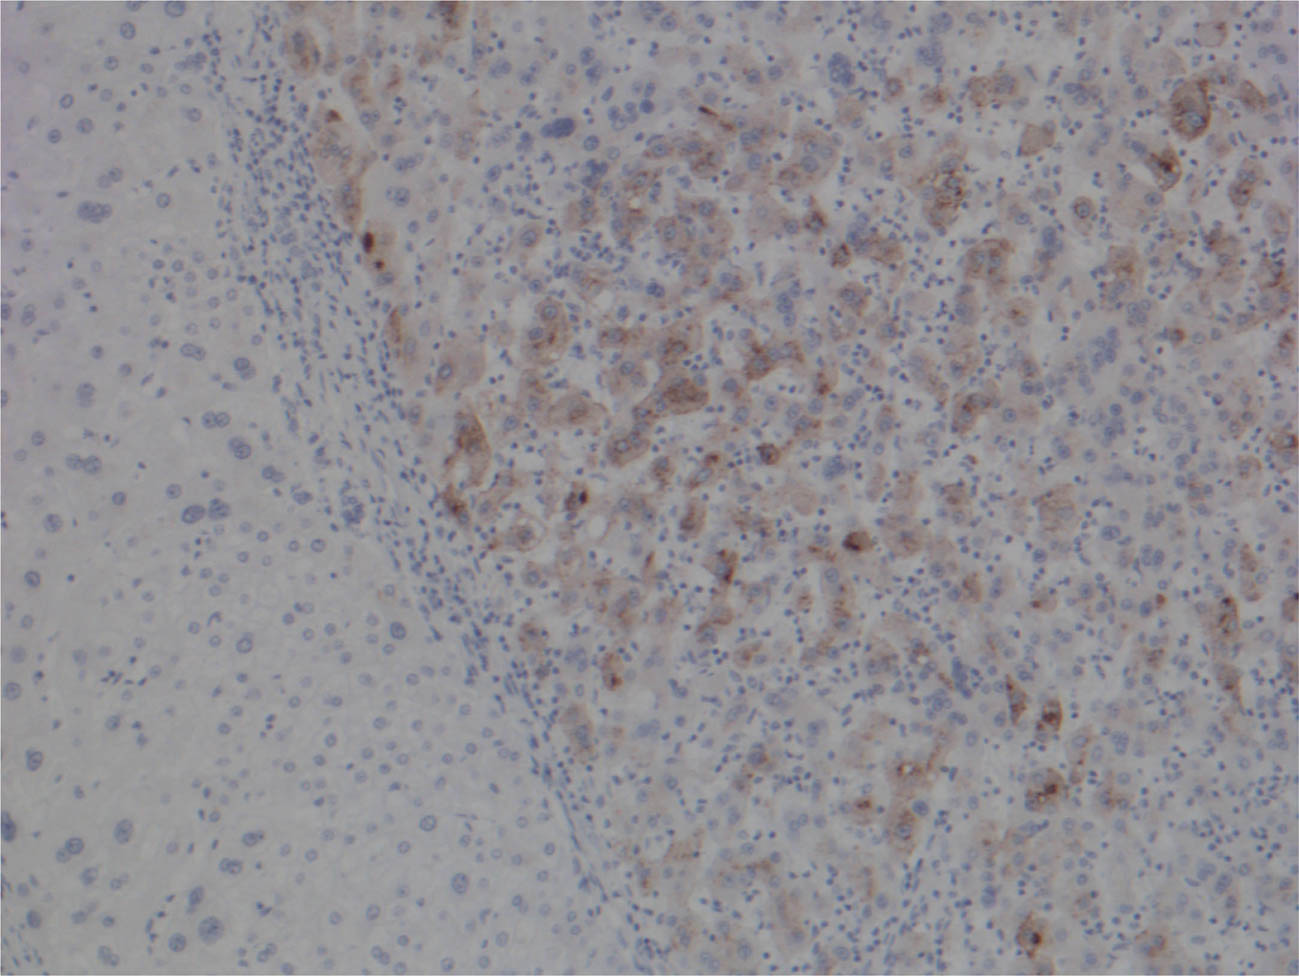

Immunohistochemical markers are widely used in hepatobiliary pathology. The most useful marker is HEP PAR-1, a marker of hepatocellular differentiation but not useful for distinction between benign and malignant hepatocytes. Glypican- 3 (Figure 3) and arginase-1 are specific markers for malignancy transformation (65). Supportive markers such as CD34 display typical capillarization of the sinusoids (Figure 4), and CD10 and pCEA demonstrate typical canalicular pattern. In addition, as an initial panel to exclude other possibilities, cytokeratins such as CK7 and CK20 are routinely used with the typical immunophenotype for HCC consisting of negativity for both markers.

Fig 3

Figure 3. Immunohistochemistry for Glypican- 3 200X. On the left, normal hepatocytes with no staining (brown pigmentation) as compared to hepatocellular carcinoma (on the right) with cytoplasmic and few nuclei staining positive (brown discoloration).